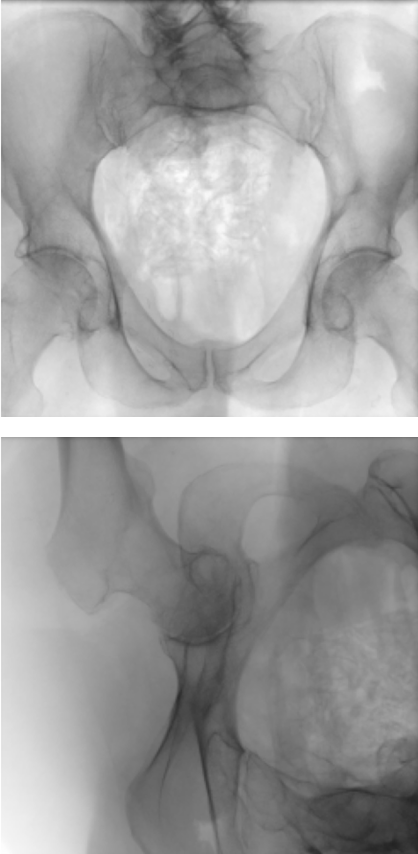

The SSM is registered to each patient from the dataset. This resulted in a base score with an average Hausdorff distance of 17.79\tsmm and a mean landmark error of 11.81\tsmm. The rotation and translation parameters obtained are assumed as the ground truth irrespective of the shape parameters. The 2D-3D reconstruction is tested by applying a random translation in the range of [-10,10]\tsmm and a rotation in the range of [-5,5] on all three axes for the SSM. The randomization is small due to the nature of the loss function being sensitive to changes only around a small region, such precision of initialization could be either provided manually or achieved with a network learning those initialization parameters. Fig. 3 shows sample outputs of our proposed method along with the quantitative results in Table 1. For evaluation, we consider only the images where the region of pelvis visible is greater than 50%percent5050\%.

Figure 3: Samples for 3D reconstruction from 2D projection images. (a) Target image, (b) Projection image with a random translation and rotation, (c) Projection image after registration, (d) Initial 3D overlay of template mesh, (e) 3D overlay of the meshes after registration, (f) NGC map after registration.